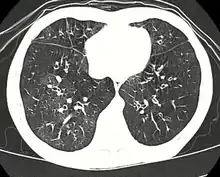

| High resolution CT scan showing bronchiolitis obliterans with mosaic attenuation, bronchiectasis, air trapping and bronchial thickening[3] | |

Early in the disease chest radiography is typically normal but may show hyperinflation.[6] As the disease progresses a reticular pattern with thickening of airway walls may be present.[4][6] HRCT can also show air trapping when the person being scanned breathes out completely; it can also show thickening in the airway and haziness in the lungs.[11] A common finding on HRCT is patchy areas of decreased lung density, signifying reduced vascular caliber and air trapping. This pattern is often described as a "mosaic pattern", and may indicate bronchiolitis obliterans.[6]